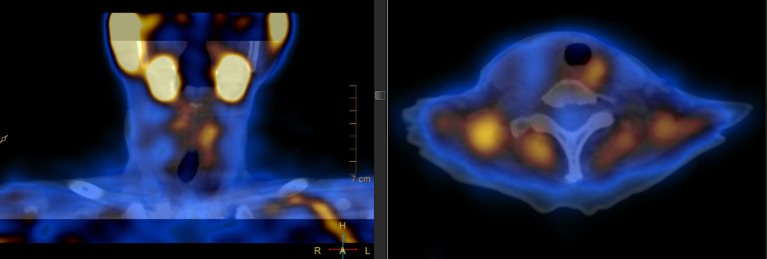

Case description: We report a female patient diagnosed with primary hyperparathyroidism, presenting with a PTH level of 192 pmol/L (1.8-8 pmol/L) and severe hypercalcemia. Preoperative 99mTc-MIBI imaging localized a left inferior hyperfunctioning parathyroid gland. Excision of the left parathyroid gland did not yield the expected fall in intraoperative parathyroid hormone (IOPTH) levels. However, an earlier ultrasound scan detected a concomitant right thyroid cyst. The cyst fluid was aspirated and sent for IOPTH assay, which revealed a high PTH level (1,060 pmol/L). The patient subsequently underwent a right hemithyroidectomy. IOPTH levels showed a 78% reduction post-surgery. Histology of the right lobe confirmed an intrathyroidal right PC amid benign thyroid follicles. The serum PTH level normalized to 1.1 pmol/L postoperatively. The patient was discharged in good condition and is undergoing annual ultrasound and PTH level surveillance.